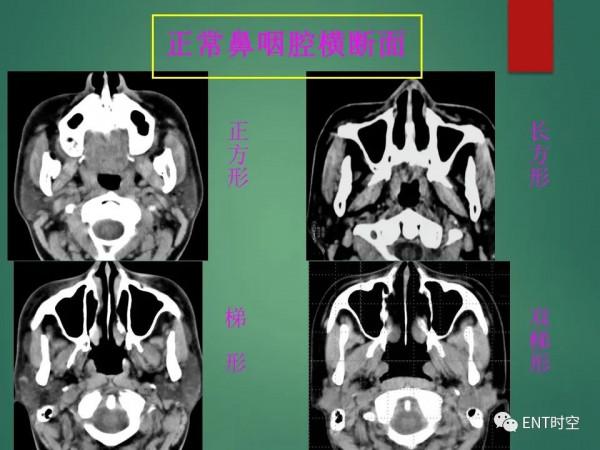

鼻和鼻竇解剖及常見病影像診斷